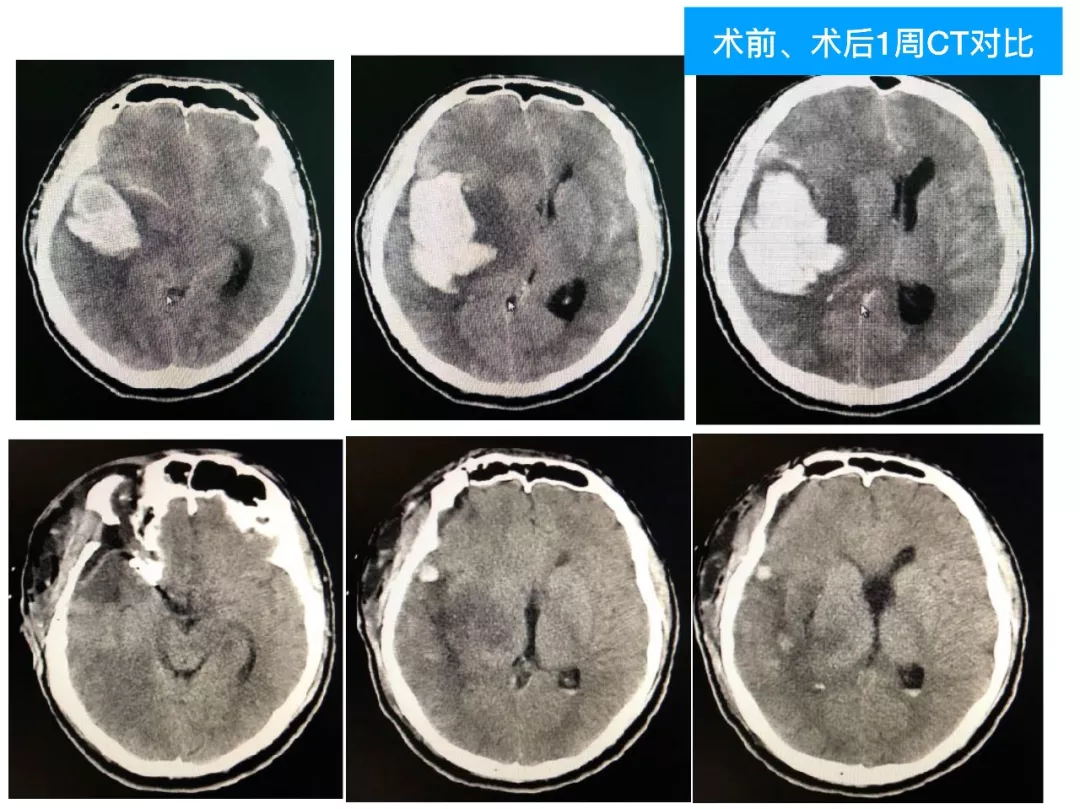

今天为大家分享的是《颅脑创伤-神经重症病例周刊》第四十九期,由天津市环湖医院神经外科五病区主任佟小光教授团队带来的:DAVF出血、脑疝急诊手术一例,欢迎阅读。

(2)DAVF即使术前很严重,及时闭塞DAVF,清除血肿,常常有好的预后;此例患者术前双侧瞳孔散大,术后回复超乎常规;